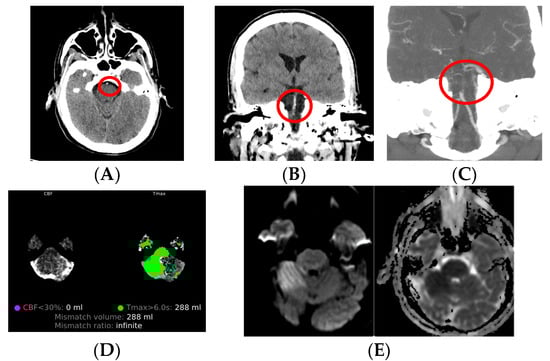

| Advantages | Disadvantages | |

|---|---|---|

| Non-contrast CT | High availability, cost-effectiveness, and rapid image acquisition; no contrast. | Ionizing radiation. Limited in posterior fossa and small lesions, as well as hyperacute and acute IS. |

| CT angiography | Locates source of thrombi or emboli and the clot dimensions in order to plan the reperfusion treatment. | Ionizing radiation. Contrast contraindications. |

| CT perfusion | Provides an accurate delimitation of the infarct core and penumbra area and thus good selection of patients for reperfusion treatment. | Ionizing radiation. Limited availability. |

| MRI | No radiation; greater sensitivity than CT; better detection of small lesions in comparison to CT. | Slower than CT; higher cost; limited availability. |

| MR angiography | Locate source of thrombi or emboli; no contrast. | Flow-dependent images may be inaccurate, unlike CTA which presents true anatomy of vessel lumen. |

| MR perfusion | Assesses brain tissue perfusion level. | Higher cost; limited availability; use of contrast. |